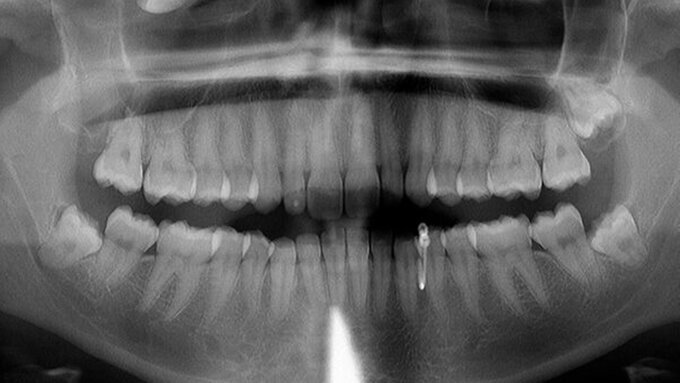

Ein 40-jähriger Patient wurde zur Extraktion der Zähne 17 und 18 überwiesen. Aus dem Jahr 2018 lag eine Panoramaschichtaufnahme vor, auf der zystische Veränderungen in beiden Kieferhöhlen (Regio 17 sowie 26) sichtbar waren (Abbildung 1). Als Verdachtsdiagnose wurde „Schleimretentionszysten" in der Patientenakte eingetragen, bevor ein aktuelles OPG angefertigt wurde.

Dort wurde eine ausgedehnte apikale Läsion an Zahn 17 sowie eine kleinere Läsion an 24 festgestellt (Abbildung 2). Beide waren klinisch druckdolent. Der Patient wurde über deren notwendige Therapie aufgeklärt. Neben der Extraktion der Zähne 18 und 17 wurden die Therapieoptionen des Zahnes 24 (Revision, Wurzelspitzenresektion oder Extraktion) erläutert. Der Patient entschied sich für die Wurzelspitzenresektion und wollte den Eingriff zu einem späteren Zeitpunkt durchführen lassen. Außerdem zeigten sich im Jahr 2022 die beiden Kieferhöhlenzysten deutlich vergrößert im Vergleich zur Voraufnahme aus 2018 – eventuell als Reaktion auf die entstandene apikale Parodontitis der benachbarten Zähne. Aufgrund der infektionsabhängigen Größenveränderung wurde die Verdachtsdiagnose in „Pseudozyste" geändert. Dem Patienten wurde aufgrund der Größe die Entfernung beider Zysten zur histologischen Absicherung empfohlen. Das wollte er sich noch überlegen.